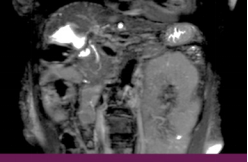

Ø 术前影像学检查

肝 S2 段及肝 S4 段见类圆形 T1WI 低、T2WI-SPAIR/DWI/ADC 高信号,较大者长径

约 10mm,界清。

T2 SPIR 冠状位